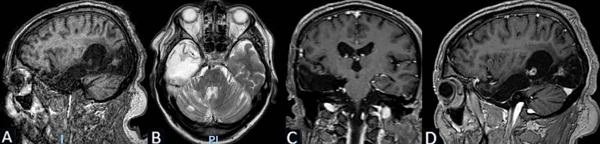

Se puede observar en la Figura 7 la RM postquirúrgica de cerebro.

Figura 7. Caso 2. RM de cerebro postquirúrgica: cambios anatómicos del lecho quirúrgico en región temporal derecha con lesión isquémica parenquimatosa secuelar occipitoparietal derecha hipointensa en T1 e hiperintensa en T2. La administración de gadolinio no pone de manifiesto refuerzos patológicos significativos. A) Secuencia T1, corte sagital. B) Secuencia T2, corte axial. C) Secuencia T1 con contraste, corte coronal. D) Secuencia T1 con contraste, corte sagital.